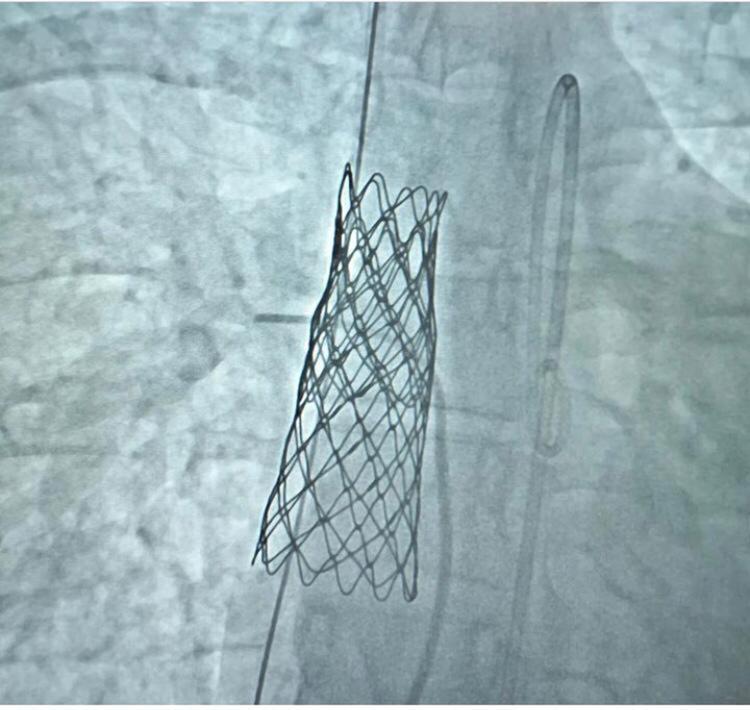

İzmir’den Prof. Dr. Nazmi Narin hocamızdan destek aldık. Tesadüfen o da buradaydı. Tomografi sonucunda kapatabileceğimize karar verdik. İşlemi başarıyla gerçekleştirdik. Ameliyatsız olarak kalpteki deliği başarılı bir şekilde stentleme yöntemiyle kapattık” diye konuştu.

Aslı Şahin’e uygulanan kapalı yöntemin, Türkiye’de sinüs venosus delik tipinde bir yetişkine yapılan ilk başarılı operasyon olduğunu belirten Astarcıoğlu, “Sinüs venosus tipi kalp açıklığı, toplardamarlar ile sol kulakçığı ayıran dokunun gelişim bozukluğu sonucu oluşur. Sinüs venosus tedavisinde son birkaç yılda önemli bir paradigma değişikliği oldu.

Bu gelişmelerin sonucu olarak kapalı stentler artık ameliyatsız olarak kapatılmasına olanak sağladı. Daha önce Ankara’da çocuk hastaya bir kez yapılmış. Kütahya’da bu işlemi gerçekleştirmiş olmaktan çok mutluyuz. Daha da ötesi hastamızın sağlığına kavuşması bizim için çok daha önemli. Operasyon yaklaşık 3 saat sürdü. Genel anestezi esnasında işlemimizi yaptık. Operasyon sonrasında hasta zaten hemen ayağa kalkabiliyor. Sonuçlar olumlu çıktığı için normal hayatına dönebilir” dedi.